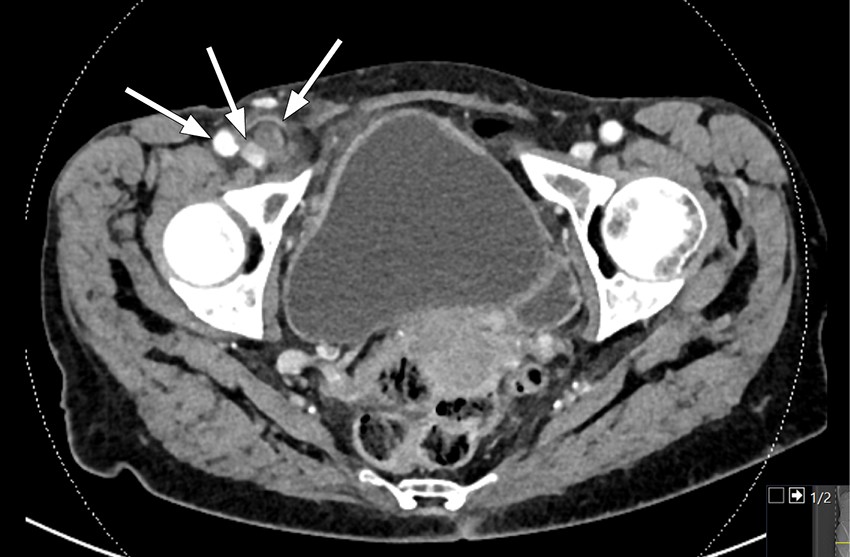

Grunnet mistanke om appendisitt ble det gjennomført CT abdomen med kontrast, der man så en tubulær struktur overfladisk i høyre fossa med tydelig omkringliggende fettvevsreaksjon inkludert fortykket peritoneum baktil. Det ble oppfattet som en inflammert appendiks og det var stedvis noe dårlig definert vegg som ga mistanke om perforert appendisitt. I tillegg så man en oppfylning i lyskekanalen på høyre side med en liten luftboble. Det var ingen sikker kommunikasjon til appendiks, men likevel sannsynlig at appendiks hadde herniert ned i femoralkanalen.

Tilstanden blir ofte diagnostisert peroperativt, men kan oppdages på CT abdomen i forkant. CT er den beste modaliteten for å fremstille de Garengeots hernie ved å kartlegge lokalisasjon og innhold i brokket. Femoralkanalen er medialt for femoralvenen og posterior for inguinalligamentet (1, 4).